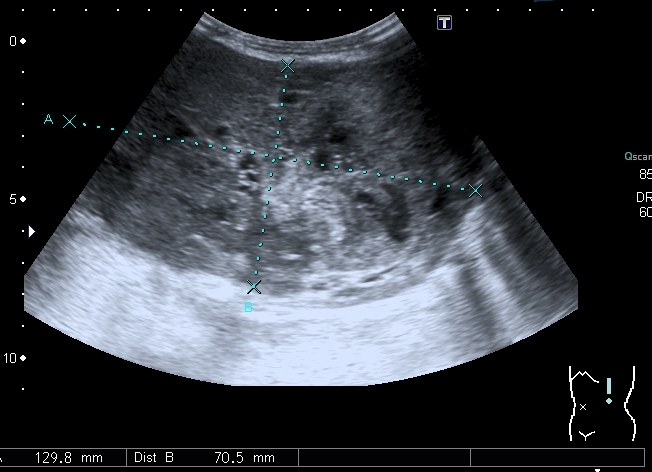

Добавляю сканы печени, я думаю они являются хорошей подсказкой о природе изменений в лёгких

Добавляю источник изменений в легких, печени и забрюшинном пространстве

Всё левое подреберье было выполнено опухолевым конгломератом, источником его я предположил левую почку, хотя разобраться , где почка, селезёнка, а тем более надпочечник я не смог.

По сложившейся тактике при обнаружении опухолевых образований мы не занимаемся морфологической верификацией, а отправляем ребёнка в головное учреждение, наверное это правильно - в лечении детских опухолей иногда бывают важны даже часы. Тем не менее , по УЗИ картине больше данных за нефробластому - есть остатки деформированной собирательной системы в области нижнего полюся образования, там же - немного ткани, похожей на нормальную почечную.

ЦДК образований в лёгких не делал, если быть откровенным, порядок находок у этого пациента был следующим: МТС в печени - изменения в нижней доле правого лёгкого - забрюшиное пространство - левая почка - левое лёгкое - правое лёгкое - рентген лёгких. Картина в комплексе была и так ясна, т.е. то, что это MTS сомнений не вызывало. Ну а после патогномоничной рентгеновской картины - вопросов тем более не было.